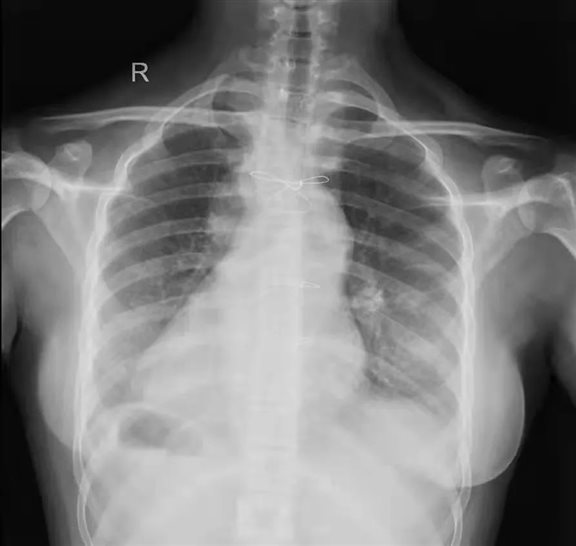

该患者33岁,患有复杂先天性心脏病,室间隔缺损,单心室,肺动脉瓣重度狭窄,镜面右位心并腹腔脏器反位,肺动脉和主动脉均发自右心室。十年前由于心衰严重无法继续生存,在外院行双向格林手术,即上腔静脉血流经肺循环氧合后进入体循环,下腔静脉血未经肺氧合直接进入体循环。